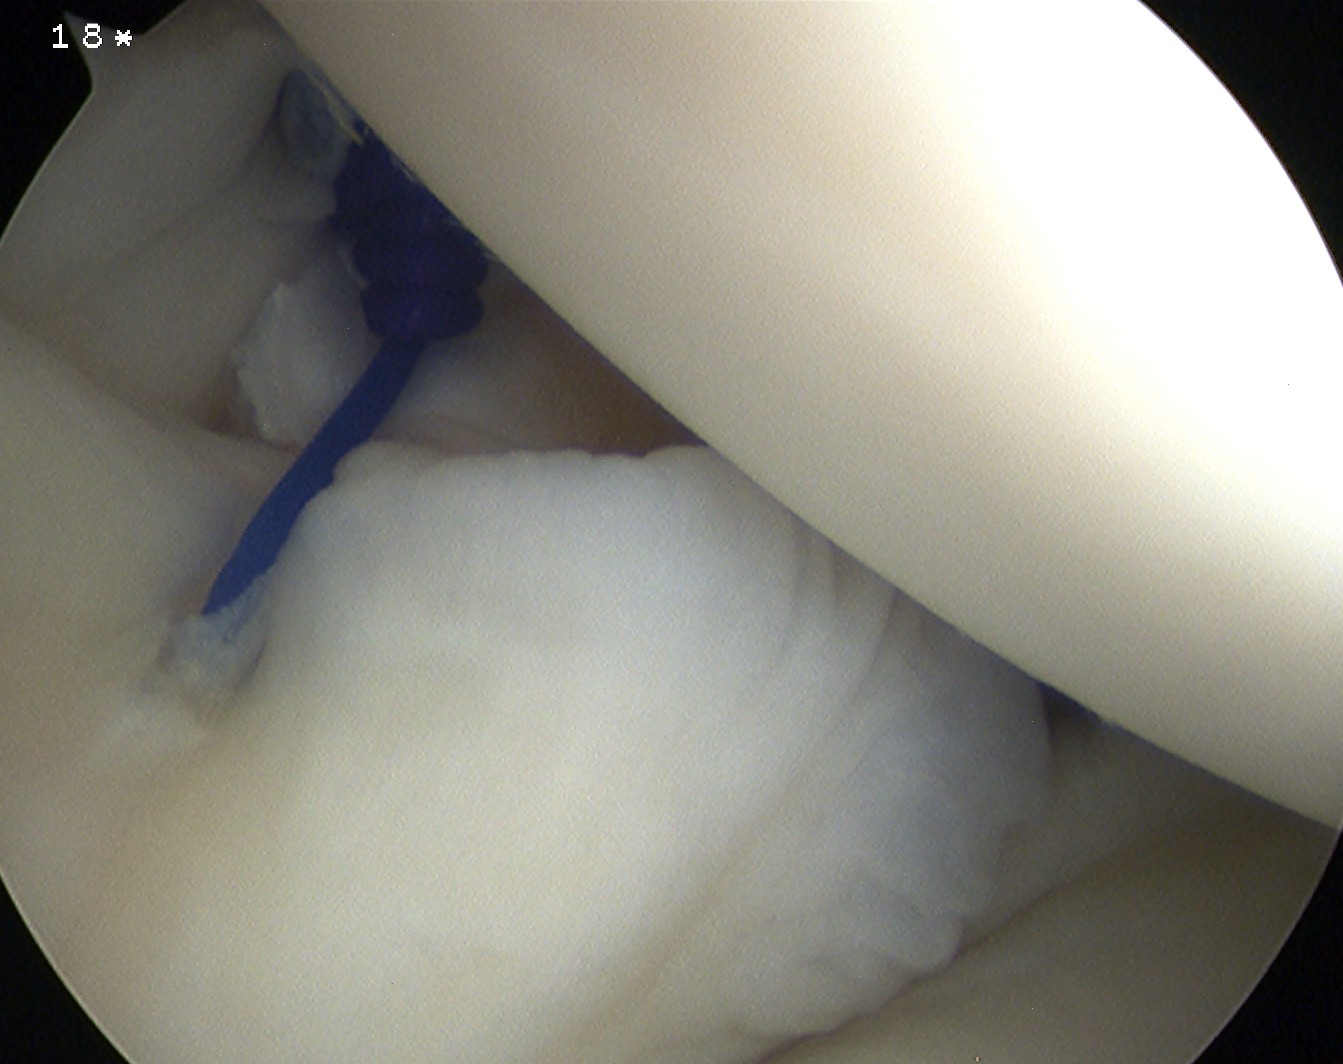

Posterior capsular plication

- option 1: Suture plicate capsule to labrum

- option 2: Anchors in glenoid and use to plicate capsule to labrum

Posterior capsular plication with suture anchors